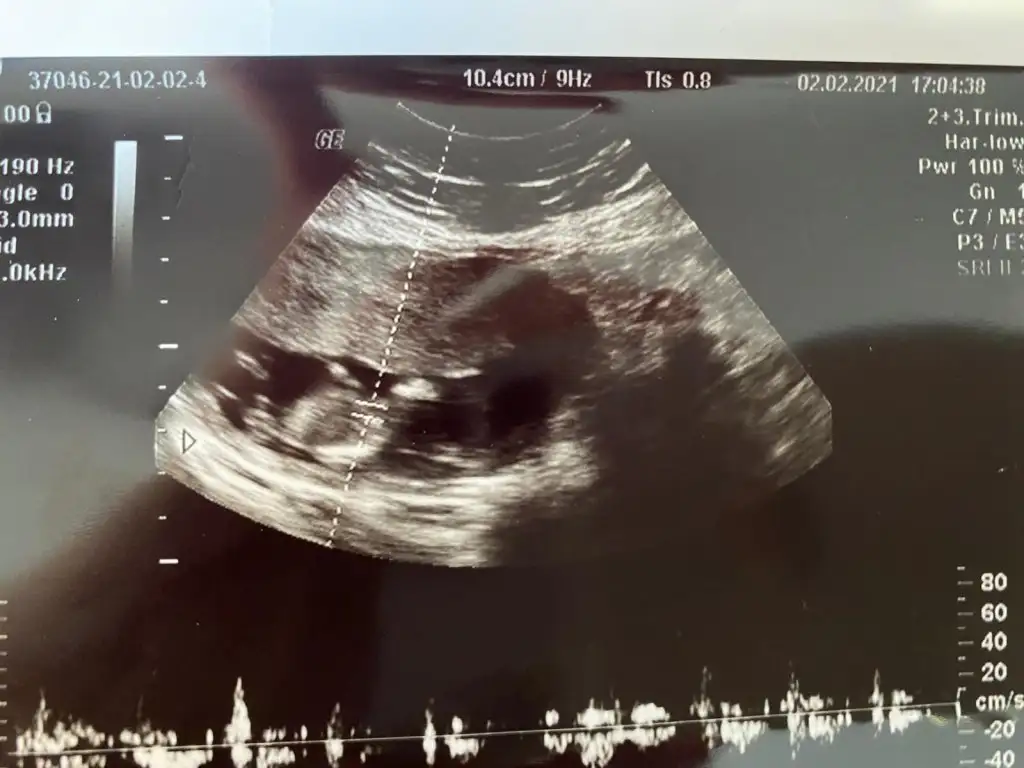

11+2 de ki karından ultrason görüntümüz bir şeyler gören varsa yazabilir mi? 😊

• WhatsApp Image 2021-02-03 at 11.18.19.webp

WhatsApp Image 2021-02-03 at 11.18.19.webp

48 KB · Görüntüleme: 226